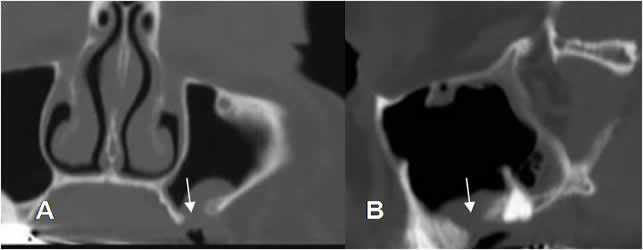

Fig 43. Enfermedad periodontal.

A: TAC axial y B: TAC reconstrucción sagital. Aumento del espacio periapical, por enfermedad periodontal.